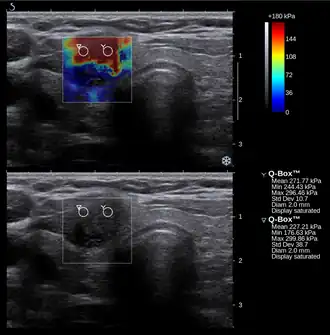

![]() Conventional ultrasonography (lower image) and elastography (supersonic shear imaging; upper image) of papillary thyroid carcinoma, a malignant cancer. The cancer (red) is much stiffer than the healthy tissue. | |

Supersonic shear imaging (SSI)

Supersonic shear imaging (SSI)[8][9] gives a quantitative, real-time two-dimensional map of tissue stiffness. SSI is based on SWEI: it uses acoustic radiation force to induce a 'push' inside the tissue of interest generating shear waves and the tissue's stiffness is computed from how fast the resulting shear wave travels through the tissue. Local tissue velocity maps are obtained with a conventional speckle tracking technique and provide a full movie of the shear wave propagation through the tissue. There are two principal innovations implemented in SSI. First, by using many near-simultaneous pushes, SSI creates a source of shear waves which is moved through the medium at a supersonic speed. Second, the generated shear wave is visualized by using ultrafast imaging technique. Using inversion algorithms, the shear elasticity of medium is mapped quantitatively from the wave propagation movie. SSI is the first ultrasonic imaging technology able to reach more than 10,000 frames per second of deep-seated organs. SSI provides a set of quantitative and in vivo parameters describing the tissue mechanical properties: Young's modulus, viscosity, anisotropy.

This approach demonstrated clinical benefit in breast, thyroid, liver, prostate, and musculoskeletal imaging. SSI is used for breast examination with a number of high-resolution linear transducers.[10] A large multi-center breast imaging study has demonstrated both reproducibility[11] and significant improvement in the classification[12] of breast lesions when shear wave elastography images are added to the interpretation of standard B-mode and Color mode ultrasound images.